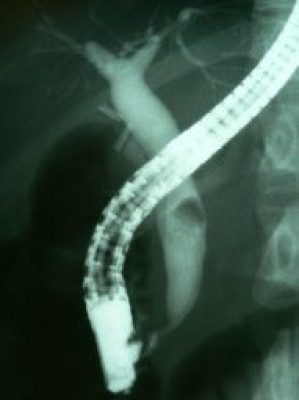

Coledocolitiasis con antecedente de colecistectomía por laparoscopía

Envíado por Dr. Carlos Miguel Zavaleta Consuegra